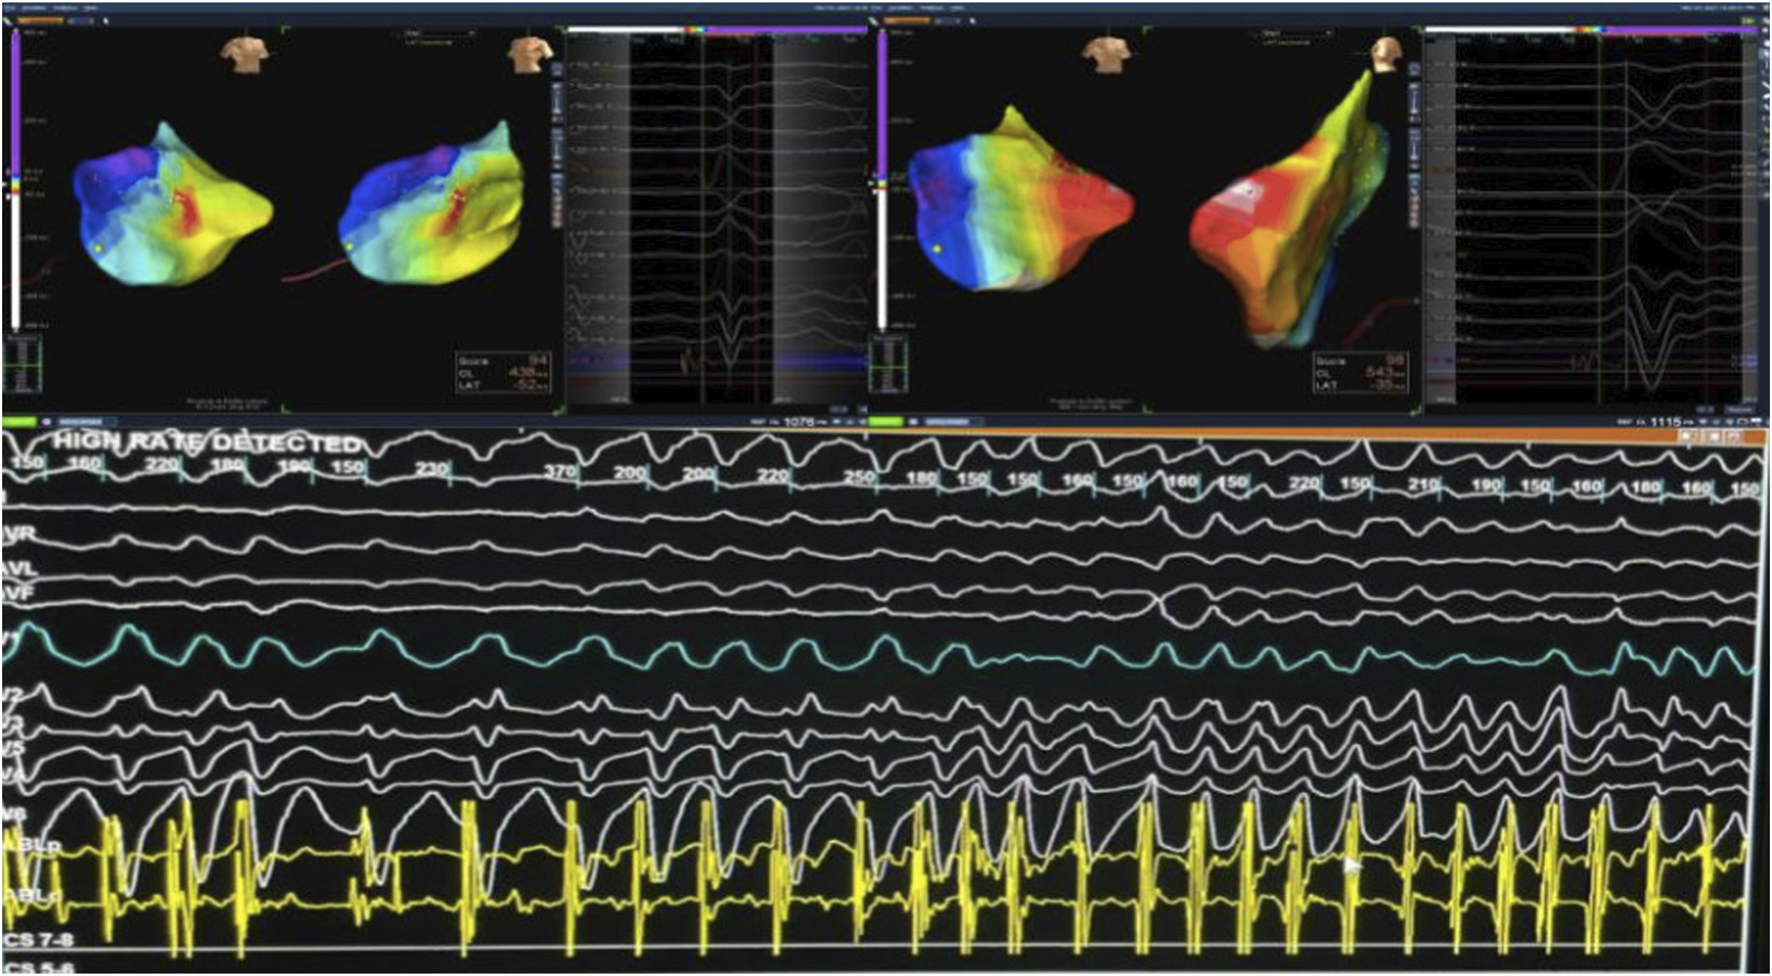

FIGURE 3

Targeting Arrhythmogenic Zones During VT mapping in The Posterior Mitral Valve Papillary Muscle. During mapping of PVCs from the posterior mitral valve papillary muscle, VT was induced and degenerated into VF, which was successfully cardioverted. Abbreviations: PVC, premature ventricular contraction; VT, ventricular tachycardia; VF, ventricular fibrillation.

Electroanatomical mapping of the LV was performed using a 3D mapping system with a contact force-sensing catheter. Transesophageal echocardiography (TEE) was utilized to visualize the papillary muscles in real time and to facilitate precise catheter positioning on the highly mobile papillary structure. Earliest activation of the clinical PVC was mapped to the mid-region of the posteromedial papillary muscle. Ablation at this site was guided by TEE to maintain stable contact on the papillary muscle and by contact force feedback to ensure adequate lesion formation. Radiofrequency lesions (with up to 40 W, irrigated catheter) were delivered, titrated to eliminate the PVCs. During ablation, the PVC frequency gradually reduced and the focus was rendered electrically inactive; no VT or VF could be induced thereafter with aggressive stimulation. The procedure achieved acute success, with complete abolition of the triggering papillary muscle ectopy and non-inducibility of any sustained arrhythmia (Figure 3).